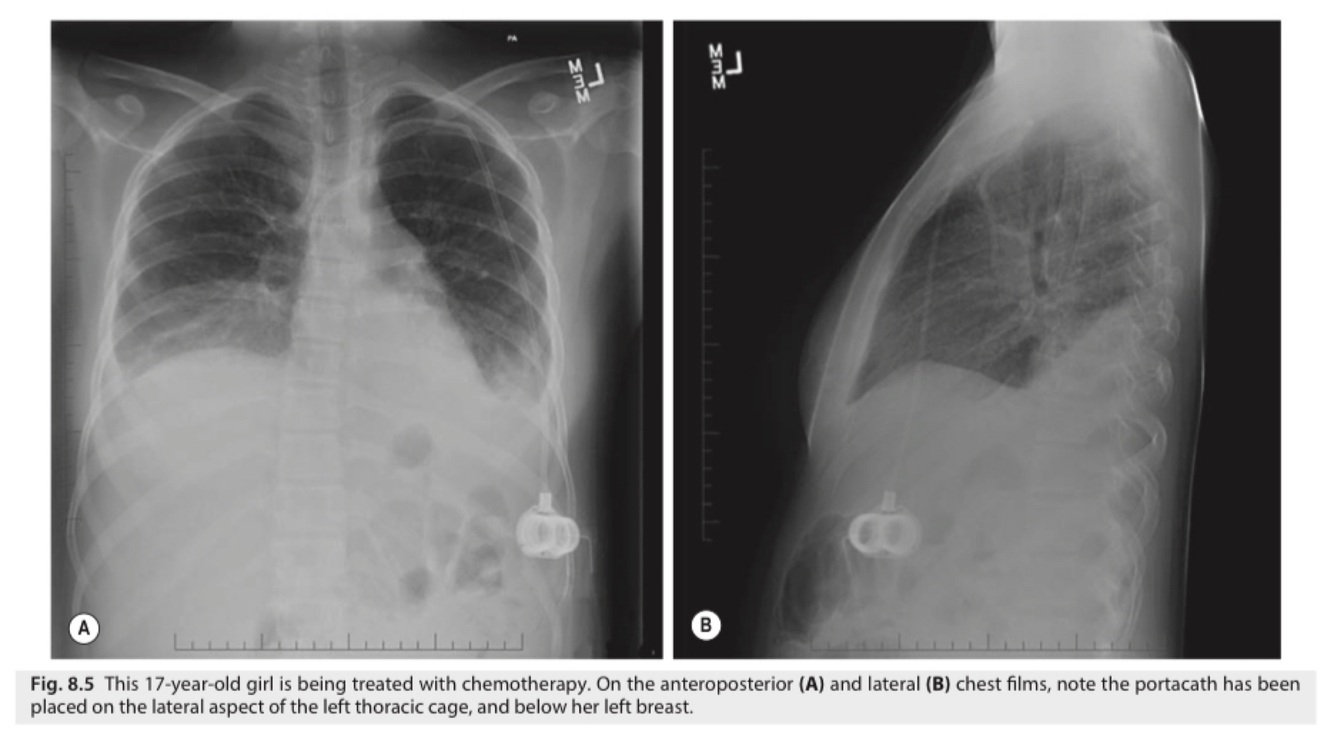

Preferred sites for port placement include the pectoral area, parasternal area, (above and medial to the areola), and the subclavicular area (medial to the anterior axillary fold).

In females with a concern for cosmesis, the low presternum area and the lateral chest wall are locations that hide the scar when the port is eventually removed.